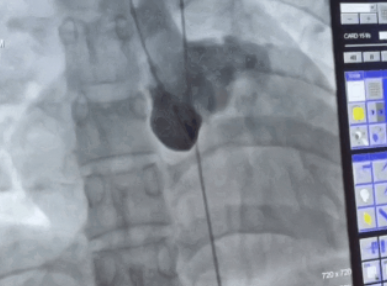

• 绵阳市三医院:成功开展首例冠状动脉瘘封堵术

绵阳市三医院:成功开展首例冠状动脉瘘封堵术 2023-06-09 作者:介入诊疗中心/白京仪